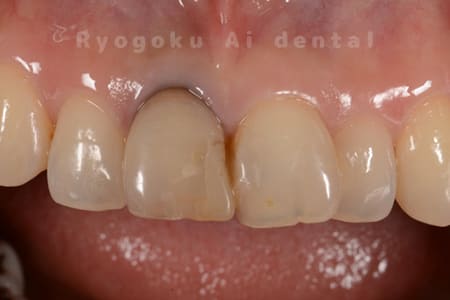

Case08

-

- 原因

- 失活歯による歯の変色

- 治療内容

- ブリーチング

- 治療費用

- 55,000円

前歯の変色が気になるとのことでご来院された患者様です。仕上がりにも満足されています。

<リスク・副作用>

治療中もしくは治療後に急に痛みが出る場合があります。感染が強い場合には痛みが激しいことがありますので、その際は痛み止め、抗生剤を処方する場合があります。

また、ダイレクトボンディングは強い衝撃などにより欠けたりすることがある。経年的に劣化(変色)してくる可能性がある。